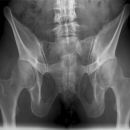

Becken a.p.

>90% aller Beckenringfrakturen lassen sich in der Übersichtsaufnahme, ggf. mit zusätzlicher Inlet und Outlet- Aufnahme (Bestimmung von Richtung und Ausmaß der Dislokation), diagnostizieren;

Beurteilungskriterien

- Symmetrie des Beckenskeletts, Position der Darmbeinkämme

- Weite und Symmetrie von Symphysenspalt (< 6mm) und ISF (< 4mm)

- Querfortsätze der unteren LWS, Kontur der Sakralforamina, ggf. CT

- Kontinuität der ilioischiadischen und iliopubischen Linie

- Azetabulumfraktur: vorderer und hinterer Pfannenrand, Pfannendachkontur, Köhlersche Tränenfigur, ggf. Zusatzaufnahmen (ap-Zielaufnahme, axiale, Ala- und Obturatoraufnahme), sowie CT

- Schenkelhalswinkel, Weite des Hüftgelenksspalt (4-5mm nach medial, 3-4mm nach kranial)

- Hüftluxation? Hüftkopf in der Beckenübersicht und in der axialen Aufnahme in der Pfanne zentriert?